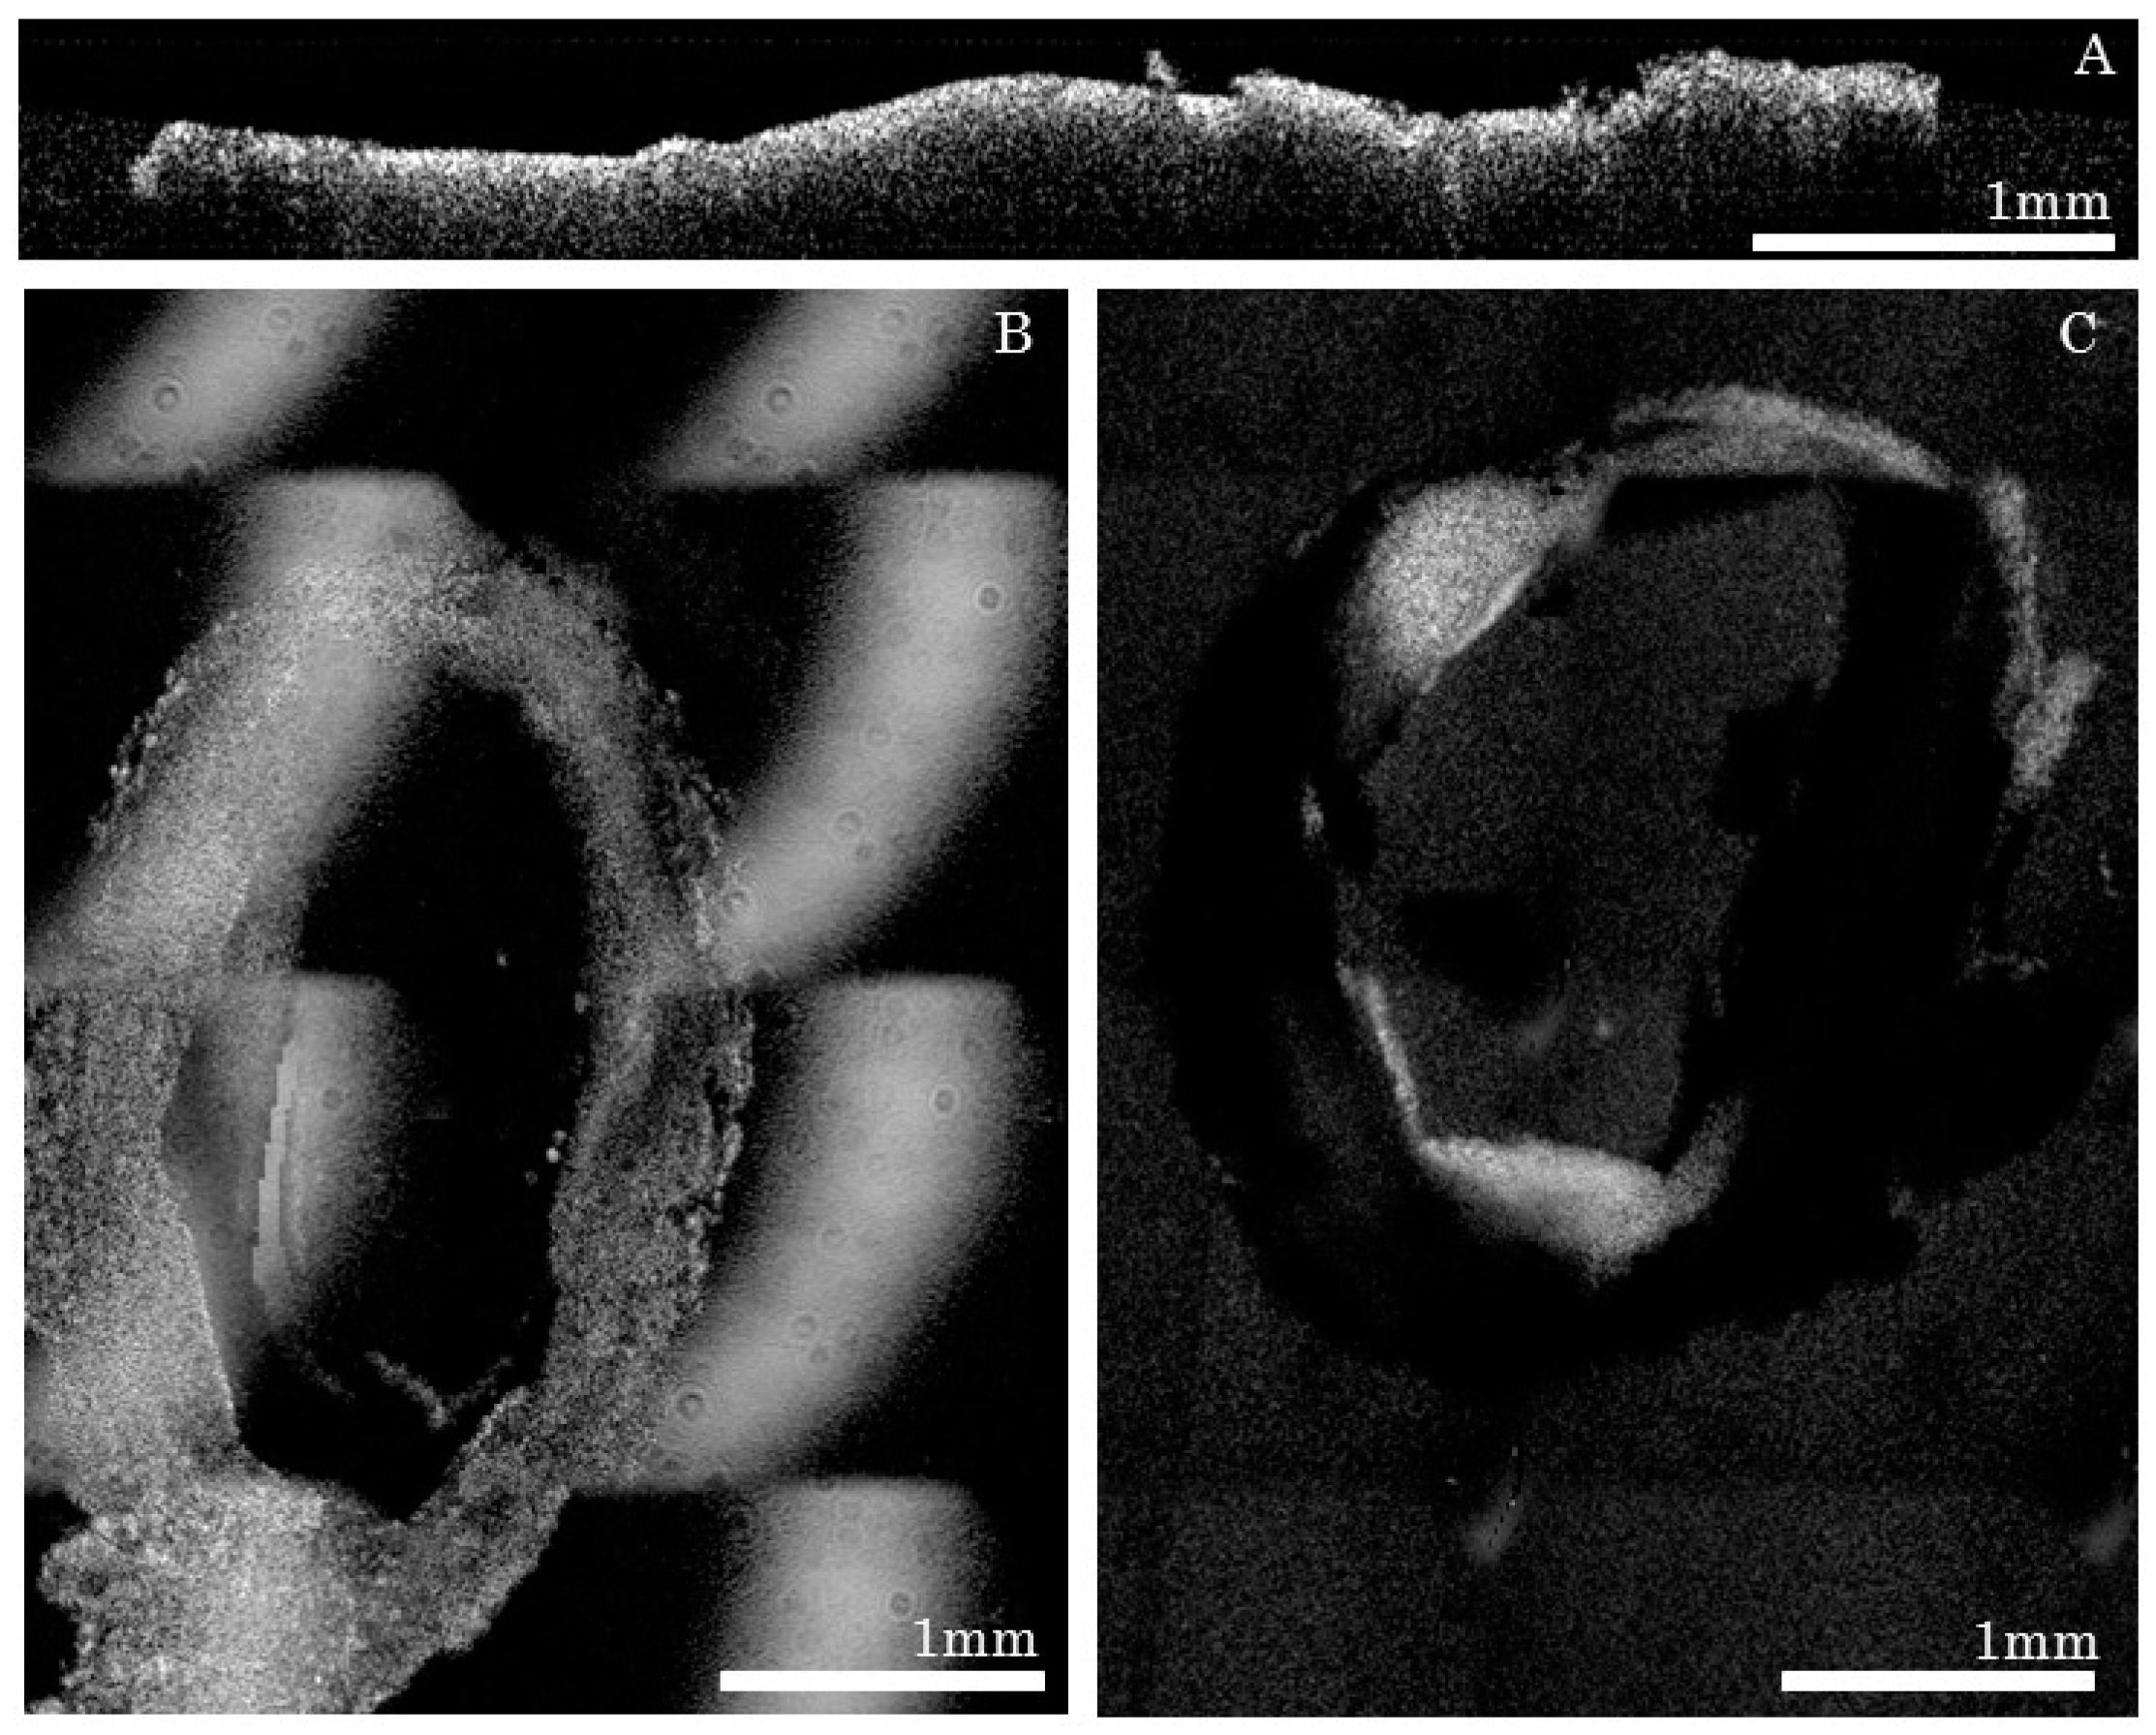

When comparing to brain imaging obtained from a similar technology, the automatic ex vivo imaging technique required careful preparation of arterial tissues, as conjunctive tissues could cause cutting artifacts (Figure 5A), thus making it challenging to obtain uniform cuts. An algorithm was applied during image acquisitions to ensure fine control of the focal depth and to avoid placing tissues in areas where OCT had instrumental artifacts (spurious reflections) or outside the focal zone of the objective (Figure 5B,C).

Figure 5. Sources of imaging artifacts and their effects during acquisitions: (A) Unevenly cut slice; (B) Artifact caused by the glass when the reference arm was not properly placed; (C) Slice that was imaged while not placed at the focal point of the lens.